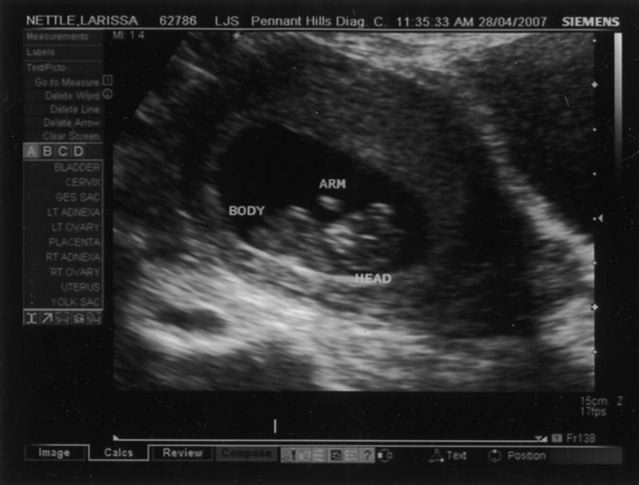

I don’t have a midwife, or a doula. Or an obstetrician, or a hospital, or even a GP that will do shared care. All I have is a due date, and a picture of a fuzzy grey blob.